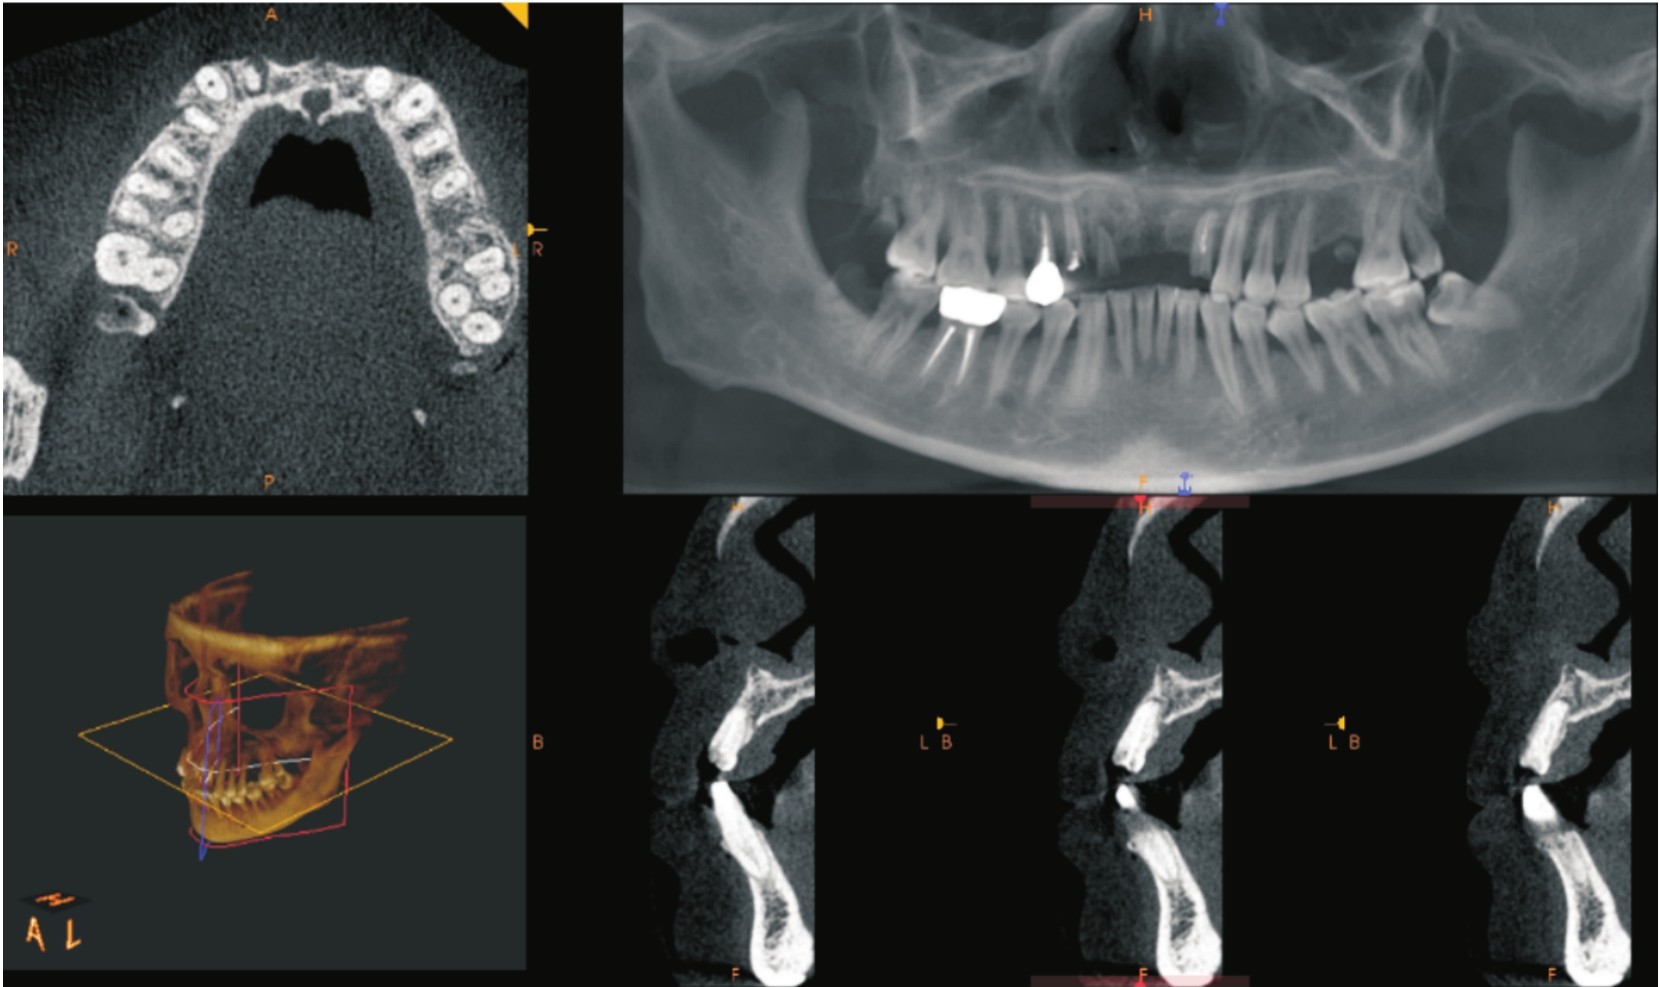

(一)导入CT图像

当导入拟种植区域的CT数据后,通常软件中会显示该解剖区域的横断面、矢状面、冠状面和三维重建图像(见图4-3)。医生可通过对不同层面的仔细观察来分析所有的解剖结构。在种植手术规划中,应详细测量术区的牙槽嵴宽度,可用骨高度,观察颌骨密度、邻牙牙根位置、下牙槽神经管走行,有无明显的骨性倒凹,动脉走行,其他颌骨病变等。对毗邻上颌窦的手术还应观察上颌窦底形态,黏膜厚度,上颌窦内有无骨嵴、囊肿、上颌窦炎等情况。对于翼上颌区域种植应详细观察上颌结节处骨宽度、翼上颌区骨高度及翼突高度,上牙槽后动脉分支走形。许多软件可以实现以不同的颜色标记重要的解剖结构,方便医生更直观地观察。

图4-3 CT数据导入Nobel Clinician种植设计软件